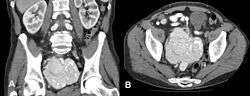

Prior to 1996 MCD carried a poor prognosis of about 2 years, due to autoimmune hemolytic anemia and non-Hodgkin's lymphoma which may arise as a result of proliferation of infected cells. The timing of diagnosis, with particular attention to the difficulty of determining the cause of B symptoms without a CT scan and lymph node biopsy, may have a significant impact on the prognosis and risk of death. Left untreated, MCD usually gets worse and becomes increasingly difficult and unresponsive to current treatment regimens.